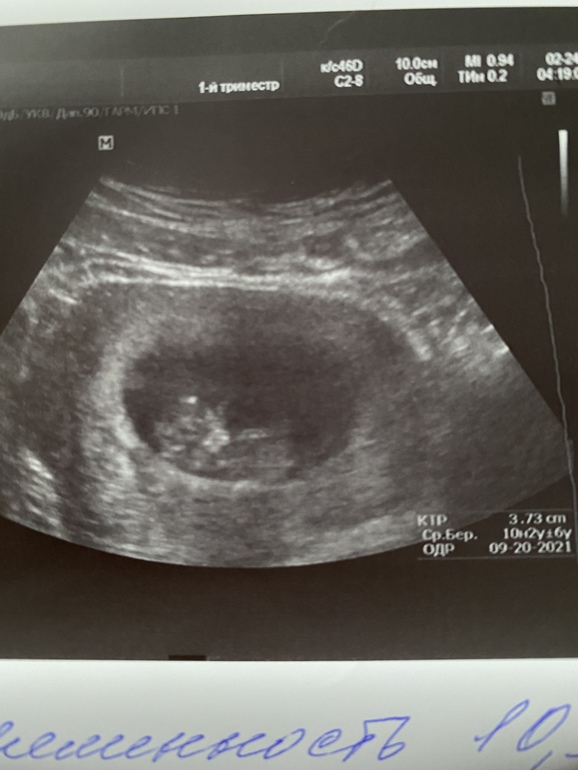

Сегодня была на узи, очень ждала встречи с нашим человеком)) по узи все ок, соответствует сроку 10.3, ктр 3.73. Сначала малышик спал, но потом стал ногами джигу-дрыгу делать 😍, после встречи и токс кажется не таким уж тяжким 😊 В пятницу едем сдавать НИПТ. Девочки всем лёгкой беременности и здоровых малышей, а кто планирует скорее увидеть заветные полосочки 🍀

Жаль фото не очень удачное